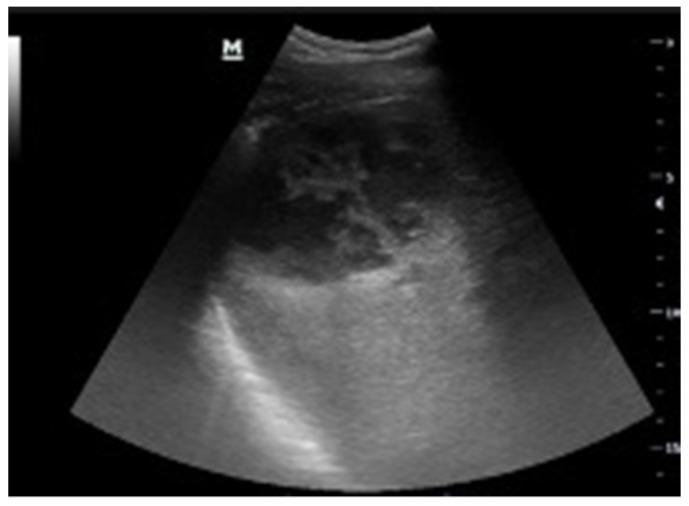

A key issue in abdominal US is the assessment of fluid, which is usually anechoic, thus appearing "black". Our approach focuses on searching for fluid in non-traumatic patients, providing a new, simplified method for point-of-care US (POCUS).

Fluid assessment is based on a three-step analysis that we can thus summarize. 1. Look for black where it should not be. This means searching for effusions or collections. 2. Check if black is too much. This means evaluating anatomical landmarks where fluid should normally be present but may be abnormally abundant. 3. Look for black that is not clearly black. This means evaluating fluid aspects, whether wholly anechoic or not (suggesting heterogeneous or corpusculated fluid).

腹部超声检查中的一个关键问题是对液体的评估,液体通常是无回声的,因此呈现“黑色”。我们的方法专注于在非创伤性患者中寻找液体,为床旁超声检查(POCUS)提供了一种新的、简化的方法。

液体评估基于我们可以总结的三步分析。1. 在不该出现黑色的地方寻找黑色。这意味着寻找积液或液性聚集。2. 检查黑色是否过多。这意味着评估正常情况下应该有液体但可能异常增多的解剖标志。3. 寻找并非明显黑色的黑色。这意味着评估液体的特征,无论是否完全无回声(提示液体不均匀或有细胞成分)。